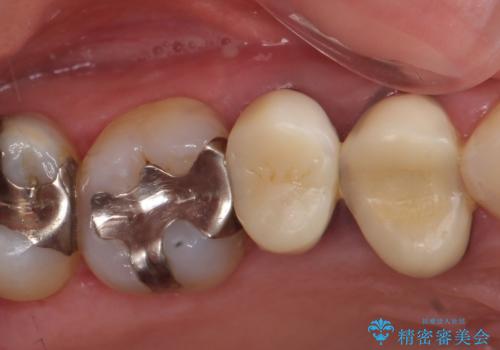

- オールセラミッククラウン…¥100,000×3、仮歯…¥10,000×3費用は治療当時の料金となります

今回用いたオールセラミッククラウンはジルコニアフレームという白い素材の上にセラミックを盛っているため、審美性が非常に高いのが特徴です。

また、ジルコニアは人工ダイヤモンドの材料にも使われているほど高い強度を持っており、そのためオールセラミッククラウンは審美性だけでなく、奥歯やブリッジの補綴も可能とするクラウンです。